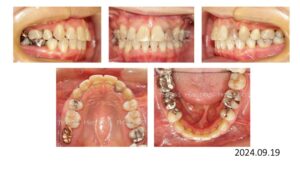

8歳の時、I市の歯科医院で、顎が狭くて歯が入りきらない、顎を拡げなければいけないといわれ、治療を開始したそうですが、6年経っても治療が終わらないどころか、写真のように全く噛み合っていないために、14歳の時にセカンドオピニオンで ひろ矯正歯科に来られました。

臼歯関係は、右が 4㎜ II級。左が 7㎜ II級で、7番しか咬合しておらず、著しい開咬を呈していました。

これは、拡大を始める前の写真ですが、口腔内写真を見る限り、拡大する必要はないです。

8歳からリンガルアーチで拡大を開始し、3年間拡大を続け、12歳でマルチブラケットを付けて治療を開始したそうですが、開咬が治らないためにアンカースクリューを4本打って治療を続けたとのことです。

こんなスクリューじゃあ何の意味もありません。

まさにやっている事がデタラメです。

ひろ矯正歯科に来られた時には、口腔内清掃状態は悪く、全ての歯が齲蝕でボロボロ、要治療でした。

治療中はブラッシング指導は一切無かったそうです。

検査、診断の結果、この患者さんは矯正のみで治療することは不可能、上下顎骨の離断が必要で外科矯正となりました。

この患者さんも歯が入らないから、顎を拡げましょうと言われ拡大を続けましたが、治療前の状態をみると、判断を誤っていることがわかります。